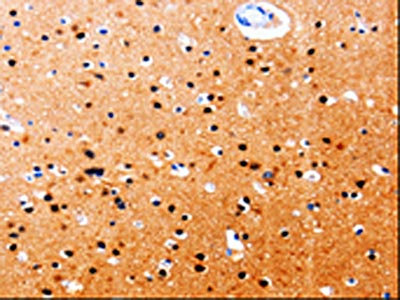

The image on the left is immunohistochemistry of paraffin-embedded Human brain tissue using CSB-PA838764(GDI1 Antibody) at dilution 1/20, on the right is treated with fusion protein. (Original magnification: ×200)